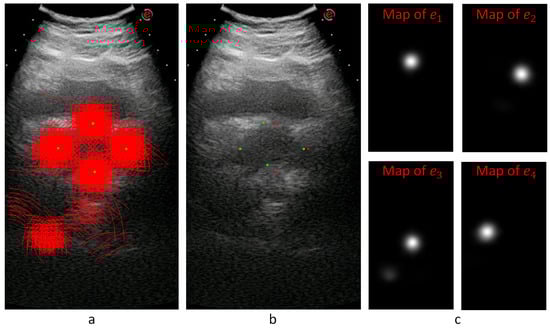

3.1. Patch Extraction

To overcome the characteristic problems of AUS images, we developed an image-patch voting system. Patch-based voting is also useful for augmenting training data. Image-patch voting makes our system robust to noise and prevents it from being affected by unrelated anatomical structures such as the bladder (see Figure 1) by generating a joint solution to the decisions made for patches of many different locations and scales. However, a patch-based system can only extract local information, which may be insufficient for AUS images due to their low SNR values. Therefore, we propose to create multiple patches of different sizes with matching centers to extract information from different scales. As shown in Figure 3, we decided to use four concentric patches, which we call quadruplet patches. The sizes of the patches in our system were 64 × 64 , 128 × 128 , 256 × 256 and 512 × 512 pixels. All patches were downsized to 64 × 64 pixels, except for the smallest scale, which was already 64 × 64 pixels. The resulting quadruplet patches cast votes for the endpoints of the ellipsoid diameters. For the voting process, we trained a novel neural model explained in Section 3.2.

The locations of the training patches were chosen randomly from a normal distribution around diameter endpoints, while evenly spaced patches were created from test images in a sliding window manner with a stride of 10 pixels. The system extracts 200 patches from each transverse and sagittal image of the training set, which can be considered as an augmentation method that increases size of the training data set. The number of patches extracted from test images changes according to the image size. Sample training patch locations are represented on Figure 4a,b, and test patch locations are represented on Figure 4c,d.

Figure 3. Patch-extraction process. For a given image location T j ( x , y ) of patient j, patches from four different scales centering ( x , y ) were extracted. All of them were downsized to the smallest scale, and the quadruplet patch P Q ( T j ( x , y ) ) was obtained.

Figure 4. Patch centers are represented on AUS images. Expert marks are shown in green, while patch centers are shown in red. (a) Random sample training patch centers on a transverse image. (b) Random sample training patch centers on a sagittal image. (c) Sample test patch centers on a transverse image. (d) Sample test patch centers on a sagittal image.